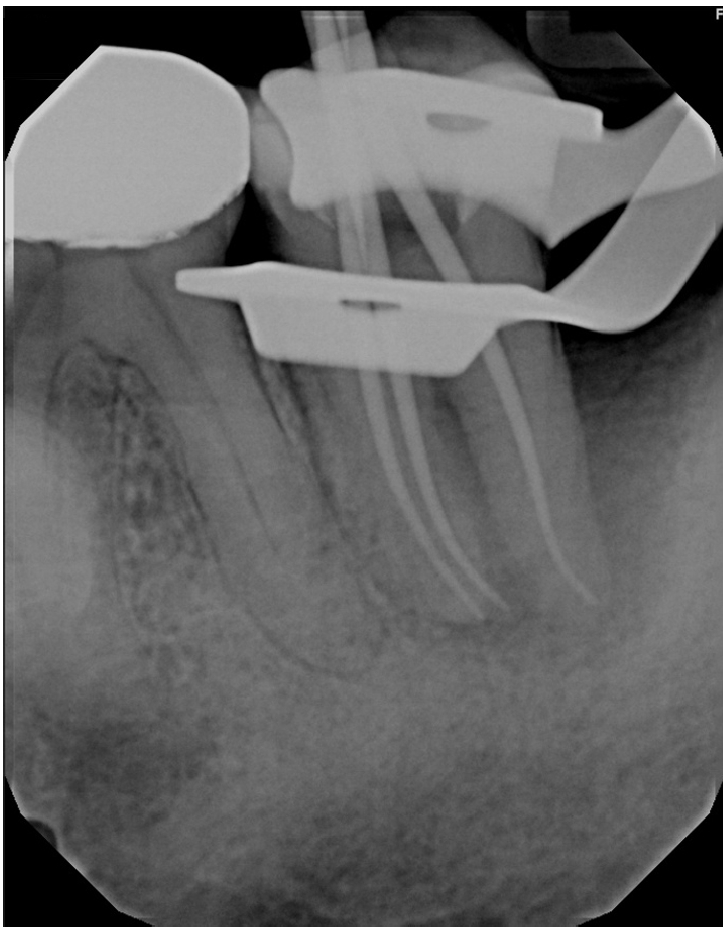

Working lengths were determined using an electronic apex locator (RootZX; J Morita, Kyoto, Japan) and confirmed with a periapical radiograph, which also showed a radiopaque fragment consistent with a cemental tear (Figure 2). The chamber was flooded with 5% sodium hypochlorite, and the canals were instrumented using size 8, 10, 15, and 20 K files, followed by a 25/.07 Primary Wave One Gold (Dentsply Sirona, Charlotte, NC, USA) reciprocating file. Irrigation was performed with 12 mL of 5% sodium hypochlorite with ultrasonic activation for 30 seconds per canal. Calcium hydroxide was placed as an intracanal medicament with a lentulo spiral, and the tooth was temporized with a sterile sponge and Cavit (3M ESPE, St. Paul, MN, USA). The patient was informed to return in 2 weeks for completion of the root canal.

Figure 2.

Working length radiograph showing radiopaque fragment consistent with a cemental tear along distal root (red arrow).

rde-2025-50-e31f2.jpg

Figure 2. Working length radiograph showing radiopaque fragment consistent with a cemental tear along distal root (red arrow).